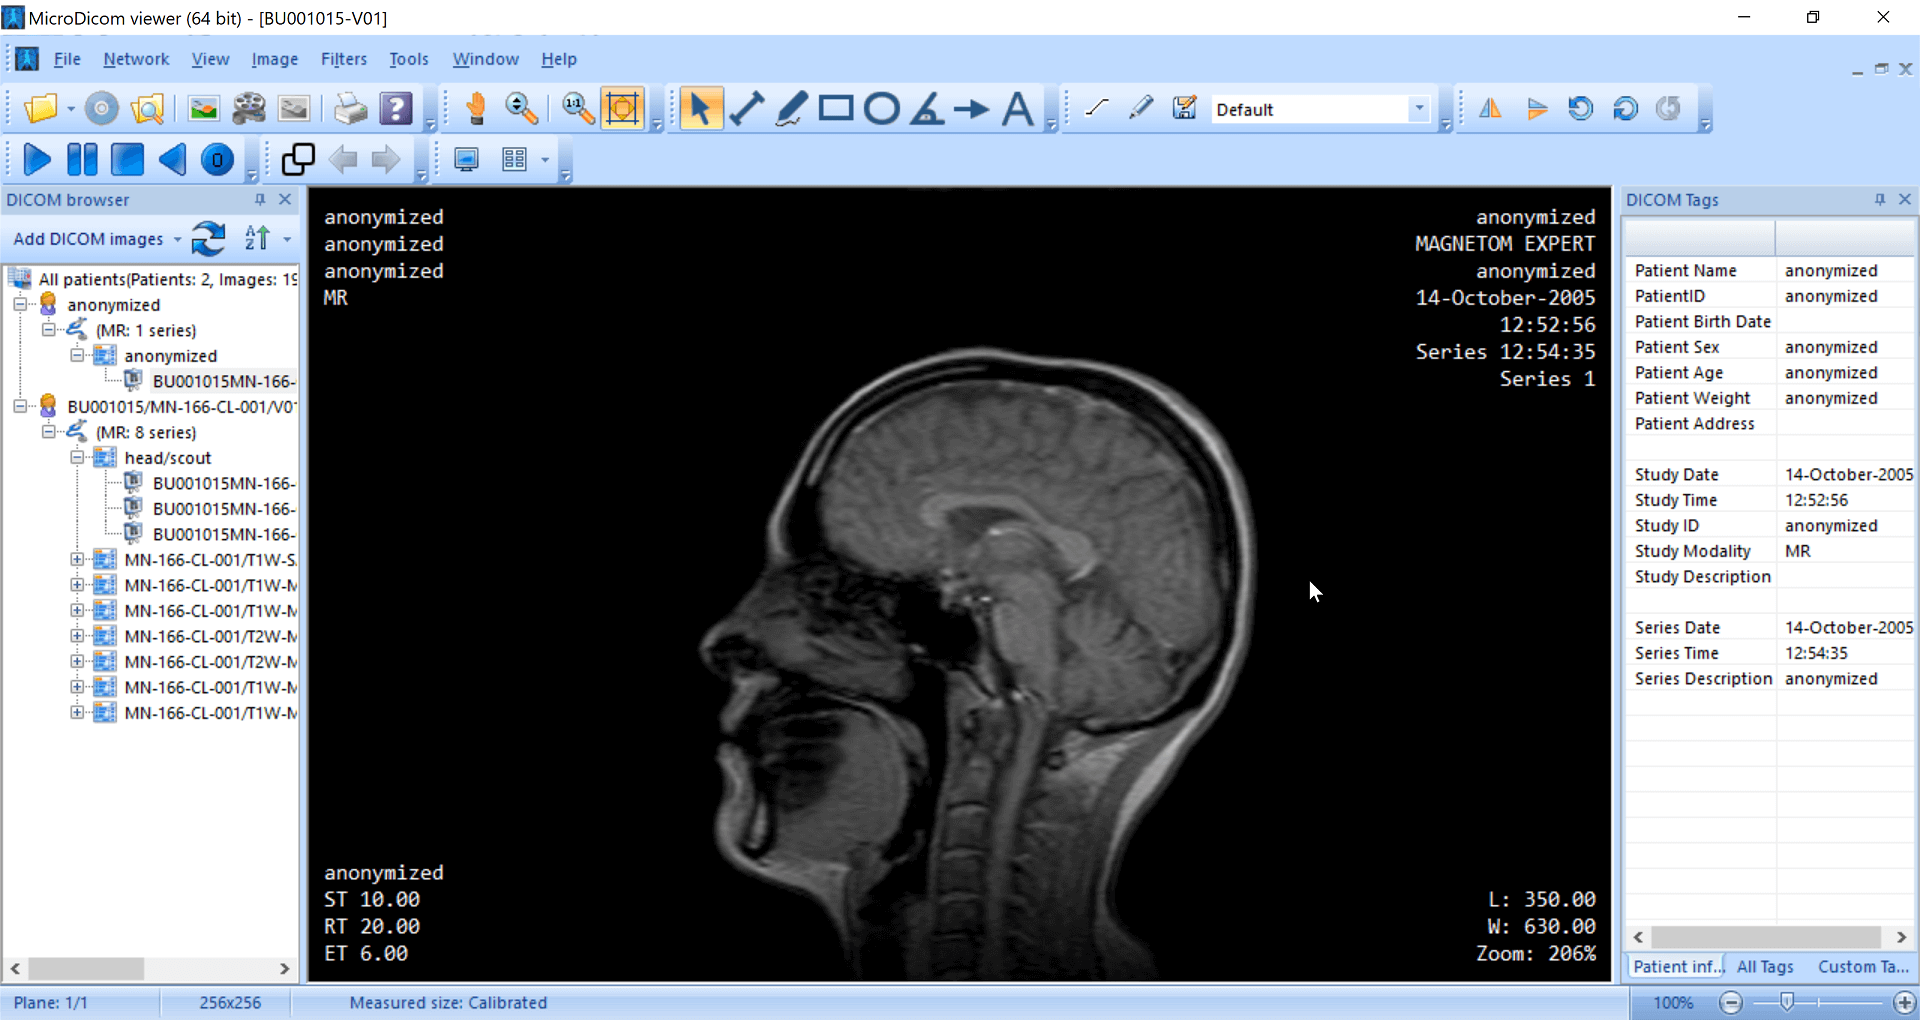

The application allows both viewing and processing of DICOM images. It can generate structured reports, and allows basic measurements, annotations, and zooming in for images. MicroDicom does not offer advanced features such as MPR and volume rendering. It can be downloaded as a potable zip file that does not require installation. This allows it to be used on any device that has a Windows OS.

| 6. | MicroDicom | Windows | Not available | N | N | N | Picture (JPEG, PNG) and movie file (AVI) formats | 14 MB | N.A. | Freeware; no CE mark or FDA approval |